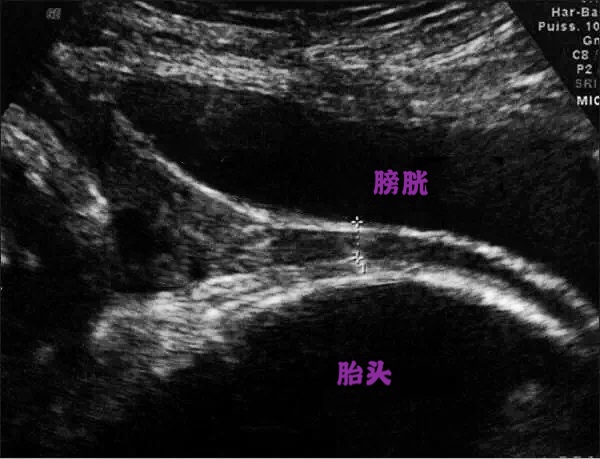

4、中晚孕期疑前壁胎盘粘连孕妇

中晚孕时特别是第一胎有剖宫产的孕妇,需要通过超声来观察胎盘粘连及其分度,中晚孕的孕妇因为有胎儿对膀胱的压迫,孕妇常会感到尿频导致更不能憋尿过多,怀疑胎盘粘连的孕妇只需要有憋尿的感觉即可,喝250ml温开水后半小时可检查